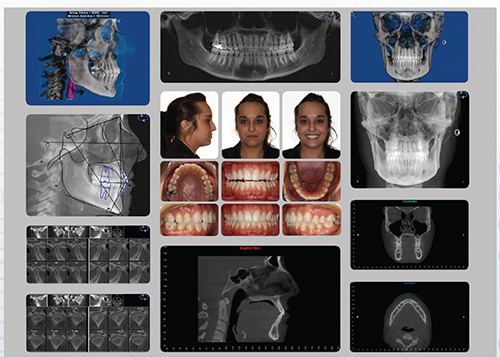

process. Hence, I published a template for use with CBVI in the

April 2010 Journal of Clinical Orthodontics.

The German template of images is intended to ensure that a

comprehensive evaluation of the data occurs for every patient,

and that the appropriate data is shared with colleagues. Each

new patient scan is scrutinized as articulated in the publication,

viewing all data in three multiplanar views (sagittal, axial and

coronal), followed by an additional review of the images created

in the German template. A very basic explanation of the purpose

of each of the views and the information gleaned from them is

described in the JCO publication.4